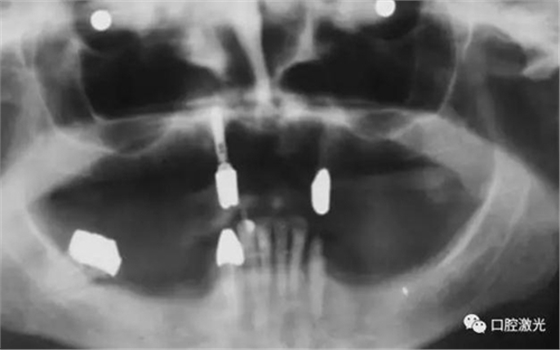

患者女性,43歲。在18年前在13位置上安裝種植體。整個(gè)上顎除23外,牙盡缺失。安裝種植體后,在種植體及23上固定套筒冠義齒。3年后患者發(fā)現(xiàn)刷牙時(shí),臨近13有大量出血現(xiàn)象。通過探針檢查發(fā)現(xiàn)深度達(dá)6mm。

對(duì)患者實(shí)施局部麻醉,隨后在種植體位置進(jìn)行翻瓣。利用塑料刮治器將肉芽組織清除干凈,并將翻瓣邊緣削薄。此時(shí)在種植體周圍可見明顯骨缺失。

如今,種植體周圍炎的治療完成已經(jīng)過去了10多年,上顎義齒的狀況沒有再出現(xiàn)問題。種植體周圍組織基本健康。